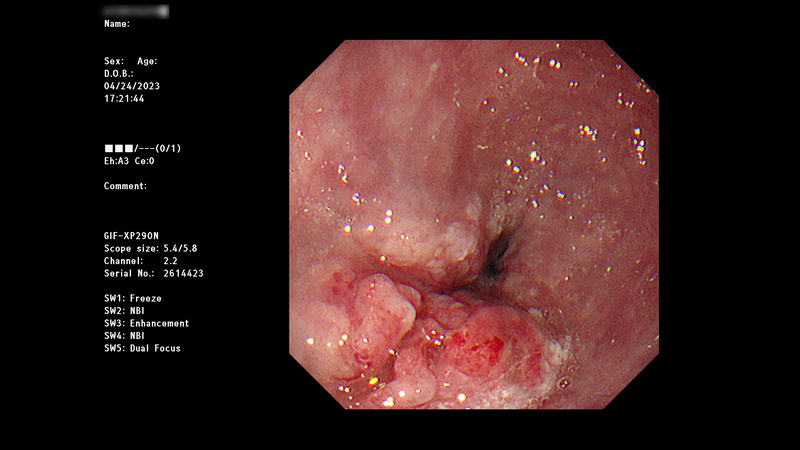

即使是第四期食道癌患者,也不是完全沒有希望。徐中平副院長指出,經過適當的治療,有些患者的病情依然可以獲顯著的改善,甚至可以達到手術治療的條件;曾有左主支氣管受腫瘤侵犯的55歲男性,經放射及化學治療後,病理報告顯示病灶顯著縮小,且無淋巴轉移。他除了建議年過四十的民眾定期健檢之外,一旦有吞嚥卡卡感覺等症狀時,務必就醫檢查,早期診斷、治療,對病人幫助最多,且大大提高成功治療的機率。

圖:圖為55歲男性食道癌患者,放化療前上內視鏡檢查消化道,發現食道中下段存在腫瘤。(徐中平提供)